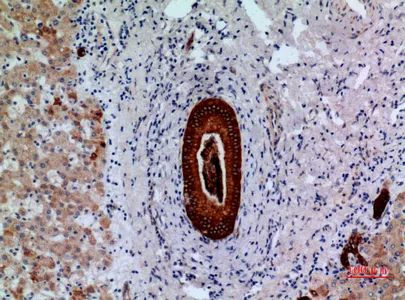

AAT Rabbit Polyclonal Antibody

Cat: APRab06383

Size1:50μl Price1:$118

Size2:100μl Price2:$220

Size3:500μl Price3:$980

Size2:100μl Price2:$220

Size3:500μl Price3:$980